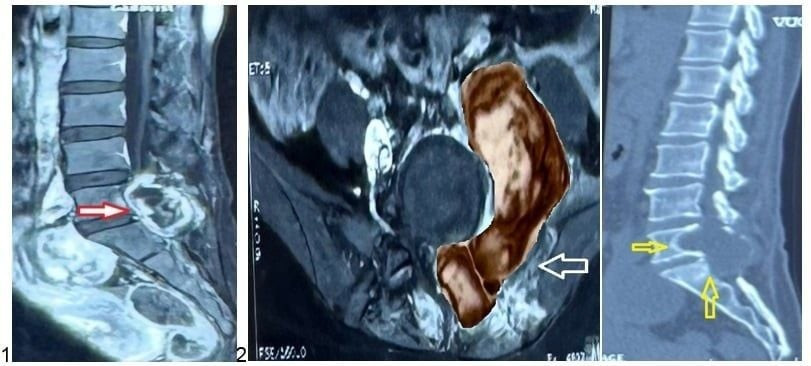

Kết quả chụp MRI cột sống thắt lưng cho thấy một khối u lớn dạng “hình quả tạ” ở vùng L5-S1, xâm lấn nhiều vị trí gồm cơ cạnh sống, cơ psoas (cơ thắt lưng chậu), thân sống, cánh chậu và cả vùng phúc mạc. BS.CKII Lê Điền Sơn, Phó trưởng khoa Ngoại Thần kinh – Bệnh viện Nhân dân 115, chia sẻ:

Hình 1, 2, 3: Ảnh chụp MRI và CT Scan trước phẫu thuật của bệnh nhân L. cho thấy khối u kích thước lớn (hình 2, mũi tên đỏ) xâm lấn các cấu trúc lân cận (hình 2, mũi tên trắng) và gây hủy xương vùng cột sống cùng (hình 3, mũi tên vàng) - Ảnh BVCC